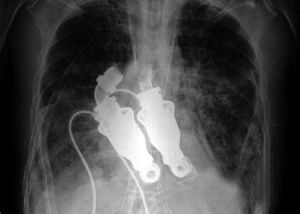

無心跳人工心臟x光片測試

發明者BillyCohn和BudFrazier稱,這種人工心臟已經在動物身上進行測試並完成了一個成功的試驗,目前沒有出現不良影響。研究所動物研究實驗室里一頭8個月大的小牛是首批接受該心臟移植的受體之一。兩位發明者說:“如果你用聽診器聽它的胸部,不會聽到心跳;如果你檢查它的動脈,也不會有脈搏;你給它做心電圖的話,只會看見一條平線。”